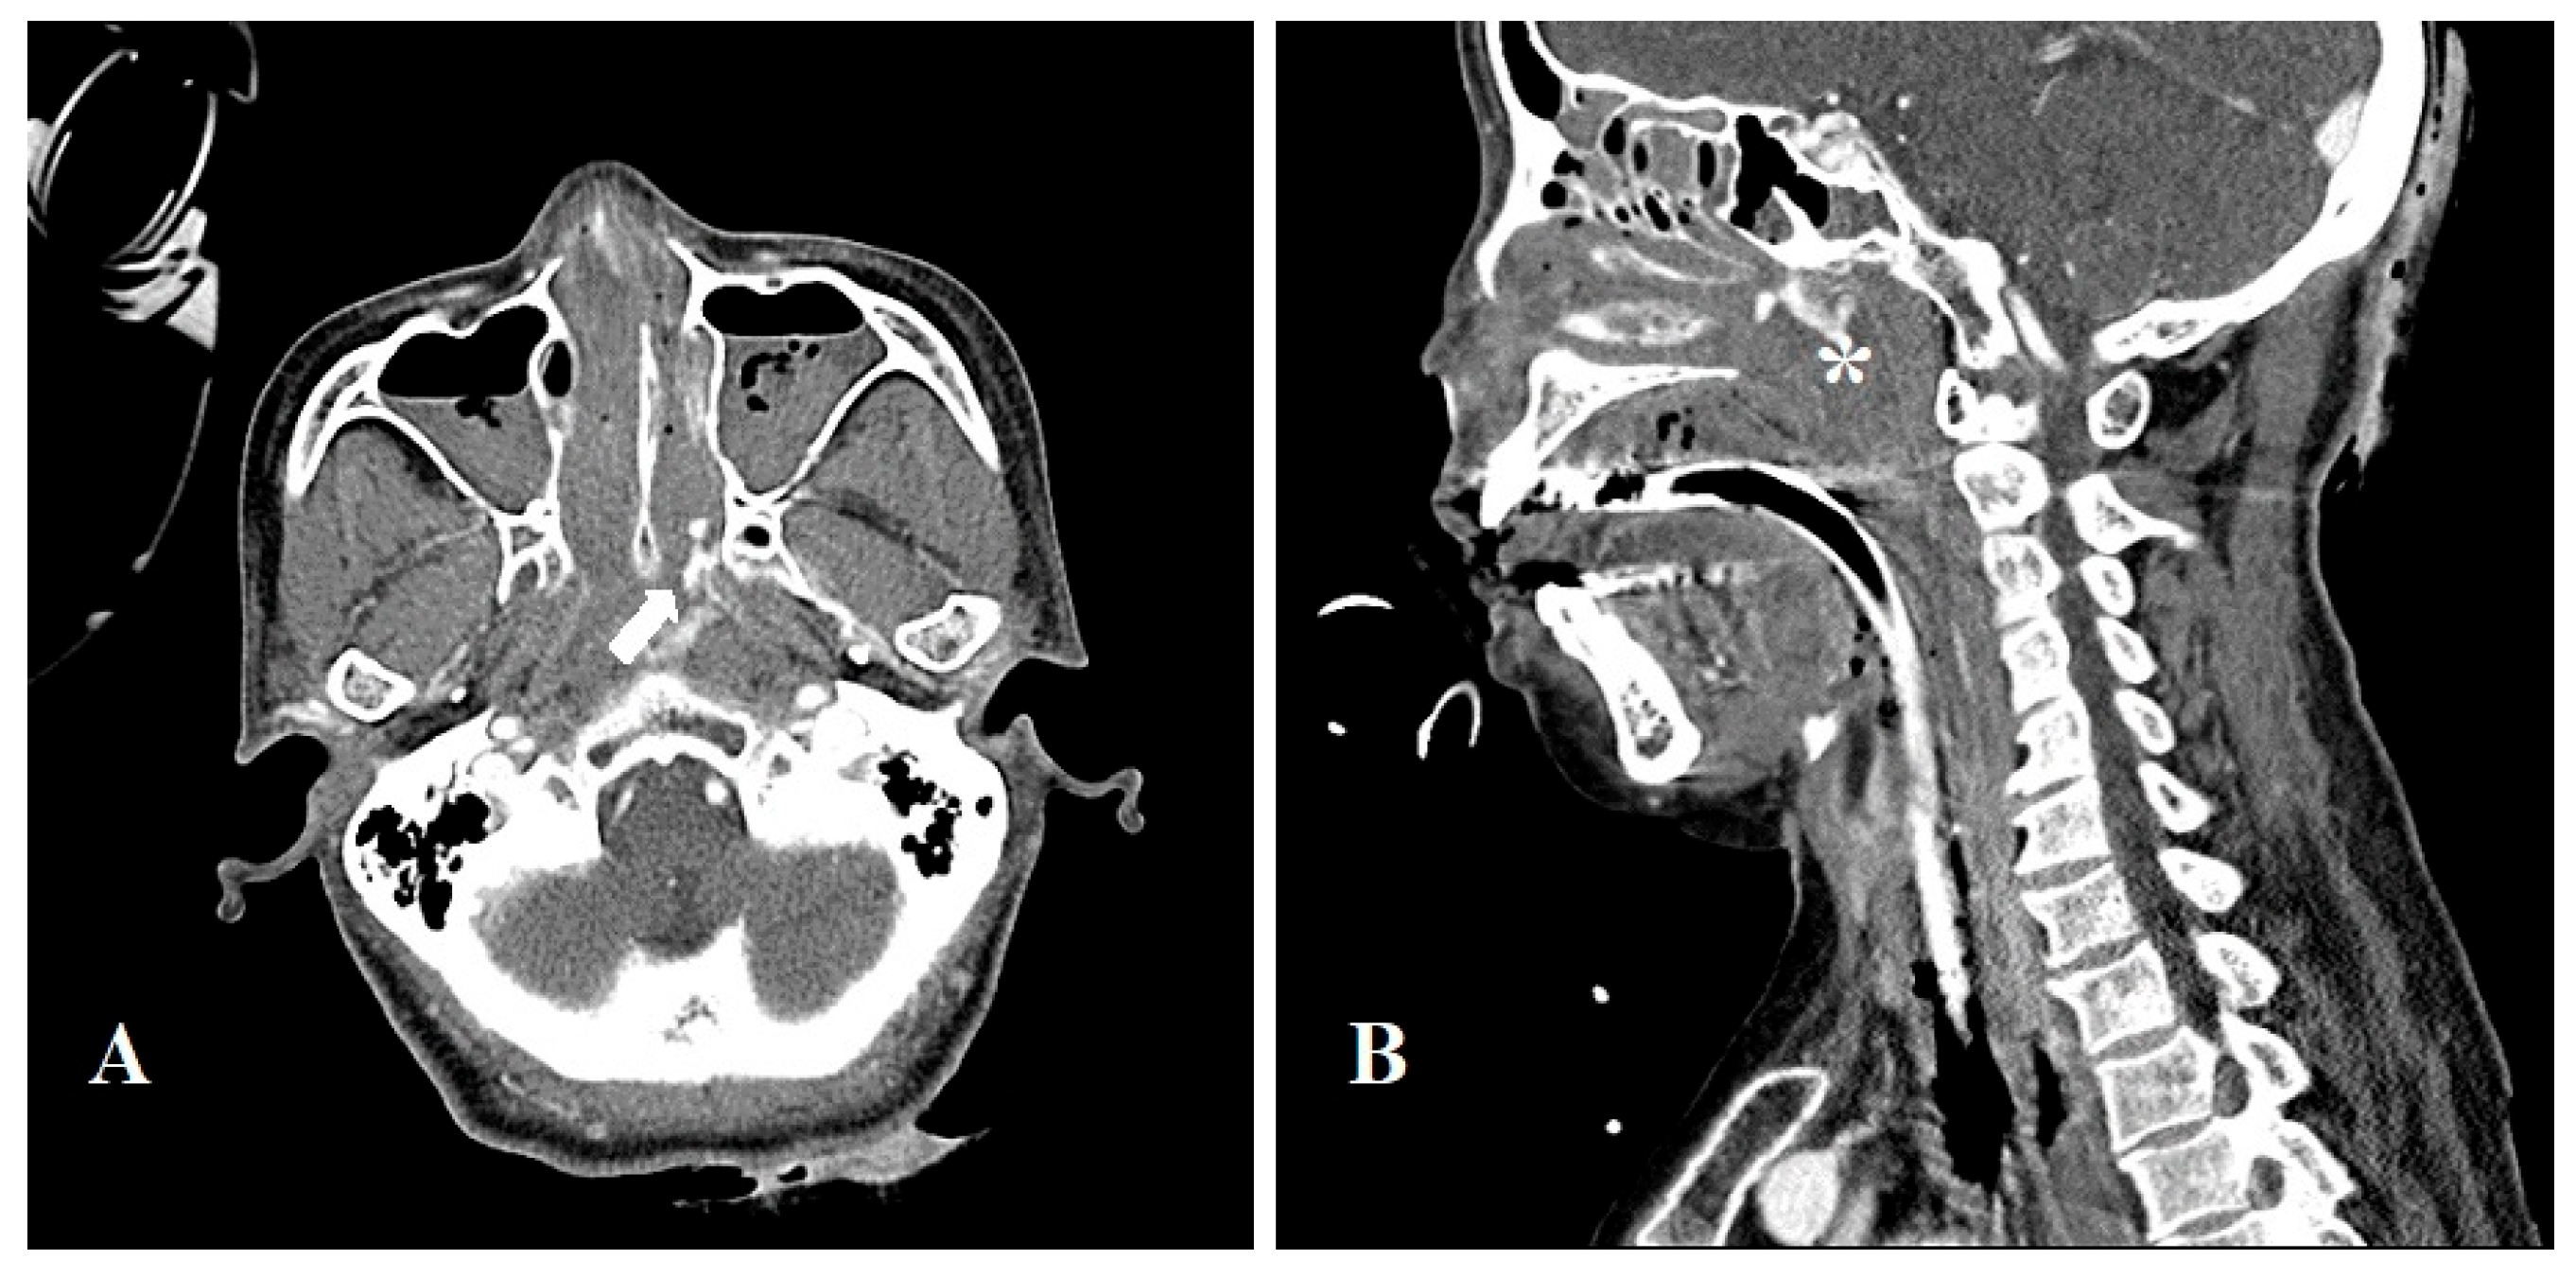

Upon arrival, the patient’s hemoglobin (Hb) level had dropped from >11 g/dL to 8.3 g/dL. An urgent aortic CT was performed, which estimated the esophagus as the bleeding focus, thus, an embolization was planned. While preparing for embolization, her blood pressure dropped to 76/47 mmHg and hemodynamic instability was shown. The patient was transferred to the intensive care unit (ICU) for vital management where her arterial blood pressure (ABP) decreased to 60/49 mmHg prompting the administration of norpin, vasopressin, dopamine, and dobutamine in their maximum dosages. As a result, systolic BP (SBP) returned to 90 mmHg facilitating an emergency angiography of the left gastric artery and celiac artery. The extravasating focus was not clear, thus the procedure was terminated following empirical embolization of the esophageal branches of the left gastric artery after which SBP and Hb decreased to 65 mmHg and 6.5 g/dL, respectively. The patient continued to vomit large quantities of blood and nasal bleeding also began, thus, transfusion was continuously administered. A collection of fresh blood was observed in the oropharynx, prompting an urgent angiography; however, there was no definite evidence of extravasation. The otorhinolaryngology department were consulted and nasopharyngeal bleeding was confirmed, 13 hours after the patient suffered her first bleed and 8.5 hours after arriving at the ER. The patient was then sedated and her nasal cavity, mouth and pharynx were found to be filled with a large hematoma. Following the removal of the hematoma, an endoscopic examination was performed. A McIvor mouth gag was placed, and a sterile round adenoid sponge was inserted into the nasopharynx to prevent blood from running down to the pharynx. Saline irrigation was performed to confirm that there was no bleeding in the oral cavity, pharynx, and larynx. While suctioning the nasal cavity, a portable rigid endoscope examination was performed to confirm left intranasal bleeding. Despite this, the exact bleeding point was not identified, so nasal packing with an inflatable tamponade (Rapid Rhino™) and a merocel sponge was carried out to arrest bleeding. Hemodynamic instability increased and SBP was reported as 50 - 60 mmHg. Arterial blood gas analysis (ABGA) revealed a pH range of 7.1 to 7.3 points, prolonged prothrombin time (PT) and activated partial thromboplastin time (aPTT). The patient’s platelet levels dropped to <8 k/µL, electrolytes were imbalanced, and an increased level of aspartate aminotransferase (AST) and alanine aminotransferase (ALT) were recorded (> 1800 IU/L and 2100 IU/L respectively). These readings indicated multiorgan failure, secondary to blood loss and transfusion. This increased the risk of postoperative mortality; thus, conservative treatment was prioritized. A contrast-enhanced neck CT scan showed enhancement from the left posterior nasal cavity to the left lateral nasopharynx with an inferior extension, suggesting the possibility of active bleeding (Figure 1). Following the stabilization of the patient’s BP and serum creatinine level, endoscopic sinus surgery was performed on the 6th day of hospitalization.

Figure 1. Contrast-enhanced Neck CT (A) Axial image; extravasation of contrast dye from the left posterior nasal cavity (arrow) (B) Extravasation of contrast dye to the left lateral nasopharynx with an inferior extension indicating the possibility of active bleeding.